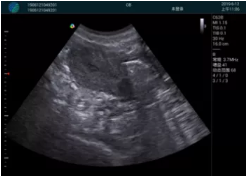

M20查看:囊內(nèi)回聲均勻,邊界清晰,囊壁光滑

M20引導(dǎo)抽吸術(shù)后囊腫消失,原區(qū)域空腔形成,脂肪層與腺體層架構(gòu)發(fā)生改變

超聲以操作簡單、定位準確、實時顯像、費用低廉等優(yōu)勢,而成為麥默通乳腺活檢治療乳腺腫塊最常見的引導(dǎo)手段,已逐步在各大醫(yī)院開展此類手術(shù)。

2、超聲的可視化操作,能準確的顯示病灶的位置、最大徑,選擇合適的刀具,決定切口的位置和方向,避開血管、減少出血危險并實時觀察乳腺病灶的切割情況,避免造成腫塊組織殘留